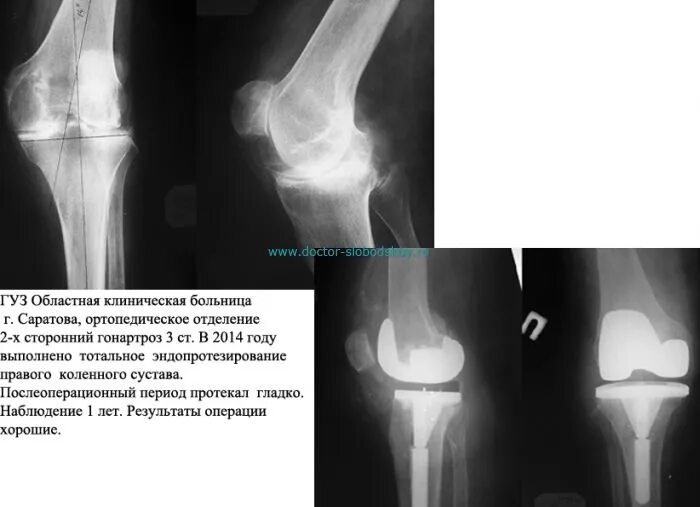

Гонартроз мрт